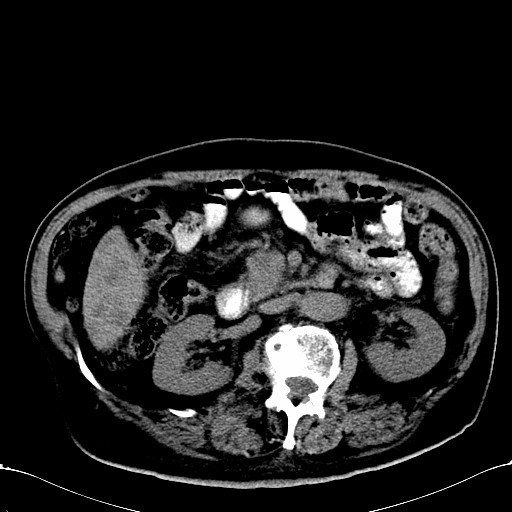

标题: CT28270:胰管扩张,肝多发占位

患者,男,75岁。

肝脏多方低密度结节,边缘模糊,考虑多发转移,胰管明显扩张,建议增强扫描钩突情况

肝脏多发低密度灶,胰头似呈低密度,胰管扩张,建议增强,

胰管显著扩张,但胆总管未见扩张征象,不太符合胰头占位!考虑慢性胰腺炎.胃窦占位并肝内转移可能!mrcp胃镜增强一起上!